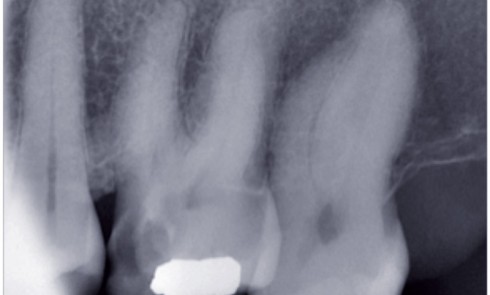

Les radiographies rétro-alvéolaires dans la CCAM